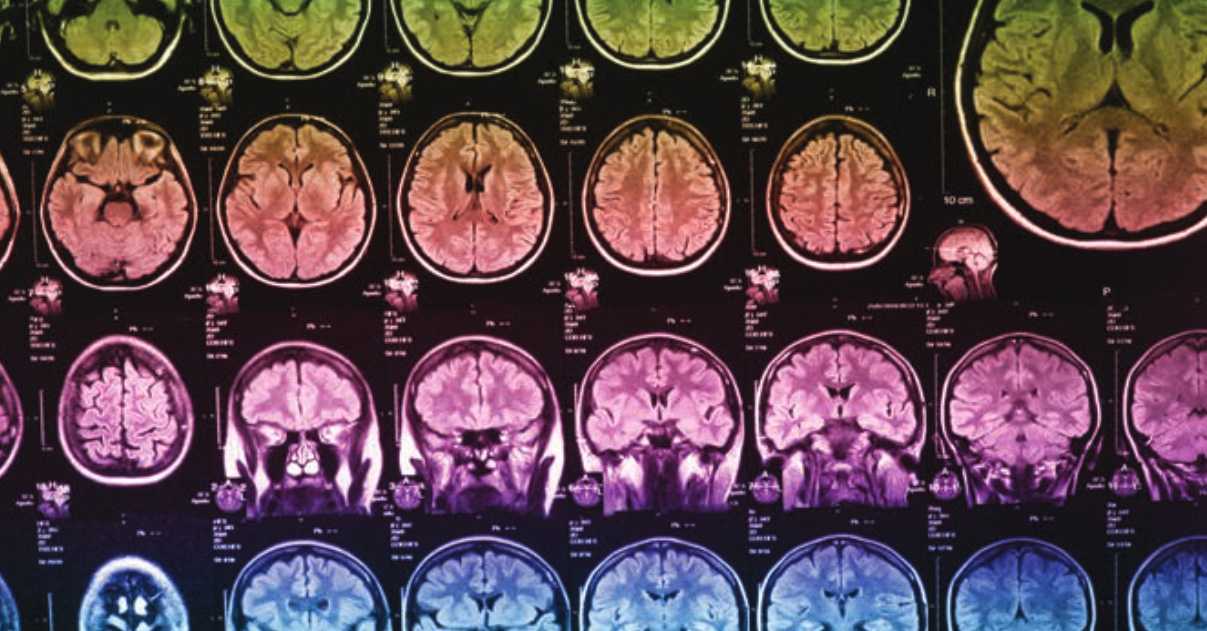

Imagerie multimodale : la neurologie en haute résolution

Les différentes techniques d’imagerie fonctionnelle étudient in vivo le fonctionnement du cerveau. L’imagerie par résonance magnétique fonctionnelle (IRMf) et la tomographie par émission de positons (TEP) mesurent les propriétés physiques de la circulation sanguine induites par l’activité neuronale. Toutes deux bénéficient d’une haute résolution spatiale de quelques millimètres mais une résolution temporelle faible de quelques secondes voire de minutes, tandis que l’électroencéphalogramme (EEG) et la magnétoencéphalographie (MEG) mesurent l’activité électromagnétique neuronale avec une très haute résolution temporelle de l’ordre de la milliseconde, mais avec une résolution spatiale plus faible de quelques millimètres au centimètre. C’est la combinaison de ces techniques qui permet d’atteindre une haute résolution temporelle et spatiale. Cette imagerie multimodale permet par exemple de délimiter la zone du foyer épileptique à traiter avant l’intervention chirurgicale, l’épilepsie induisant des variations de débit sanguin. Implanté sur le site du GHE, le Cermep est la plateforme d’imagerie in vivo des HCL ouverte aux praticiens et chercheurs du monde académique et industriel. Elle combine la multimodalité des imageries, la capacité de conduire des recherches en imagerie en lien avec des laboratoires associés, ainsi qu’une radiopharmacie permettant le développement et la production de molécules radioactives radiopharmaceutiques.